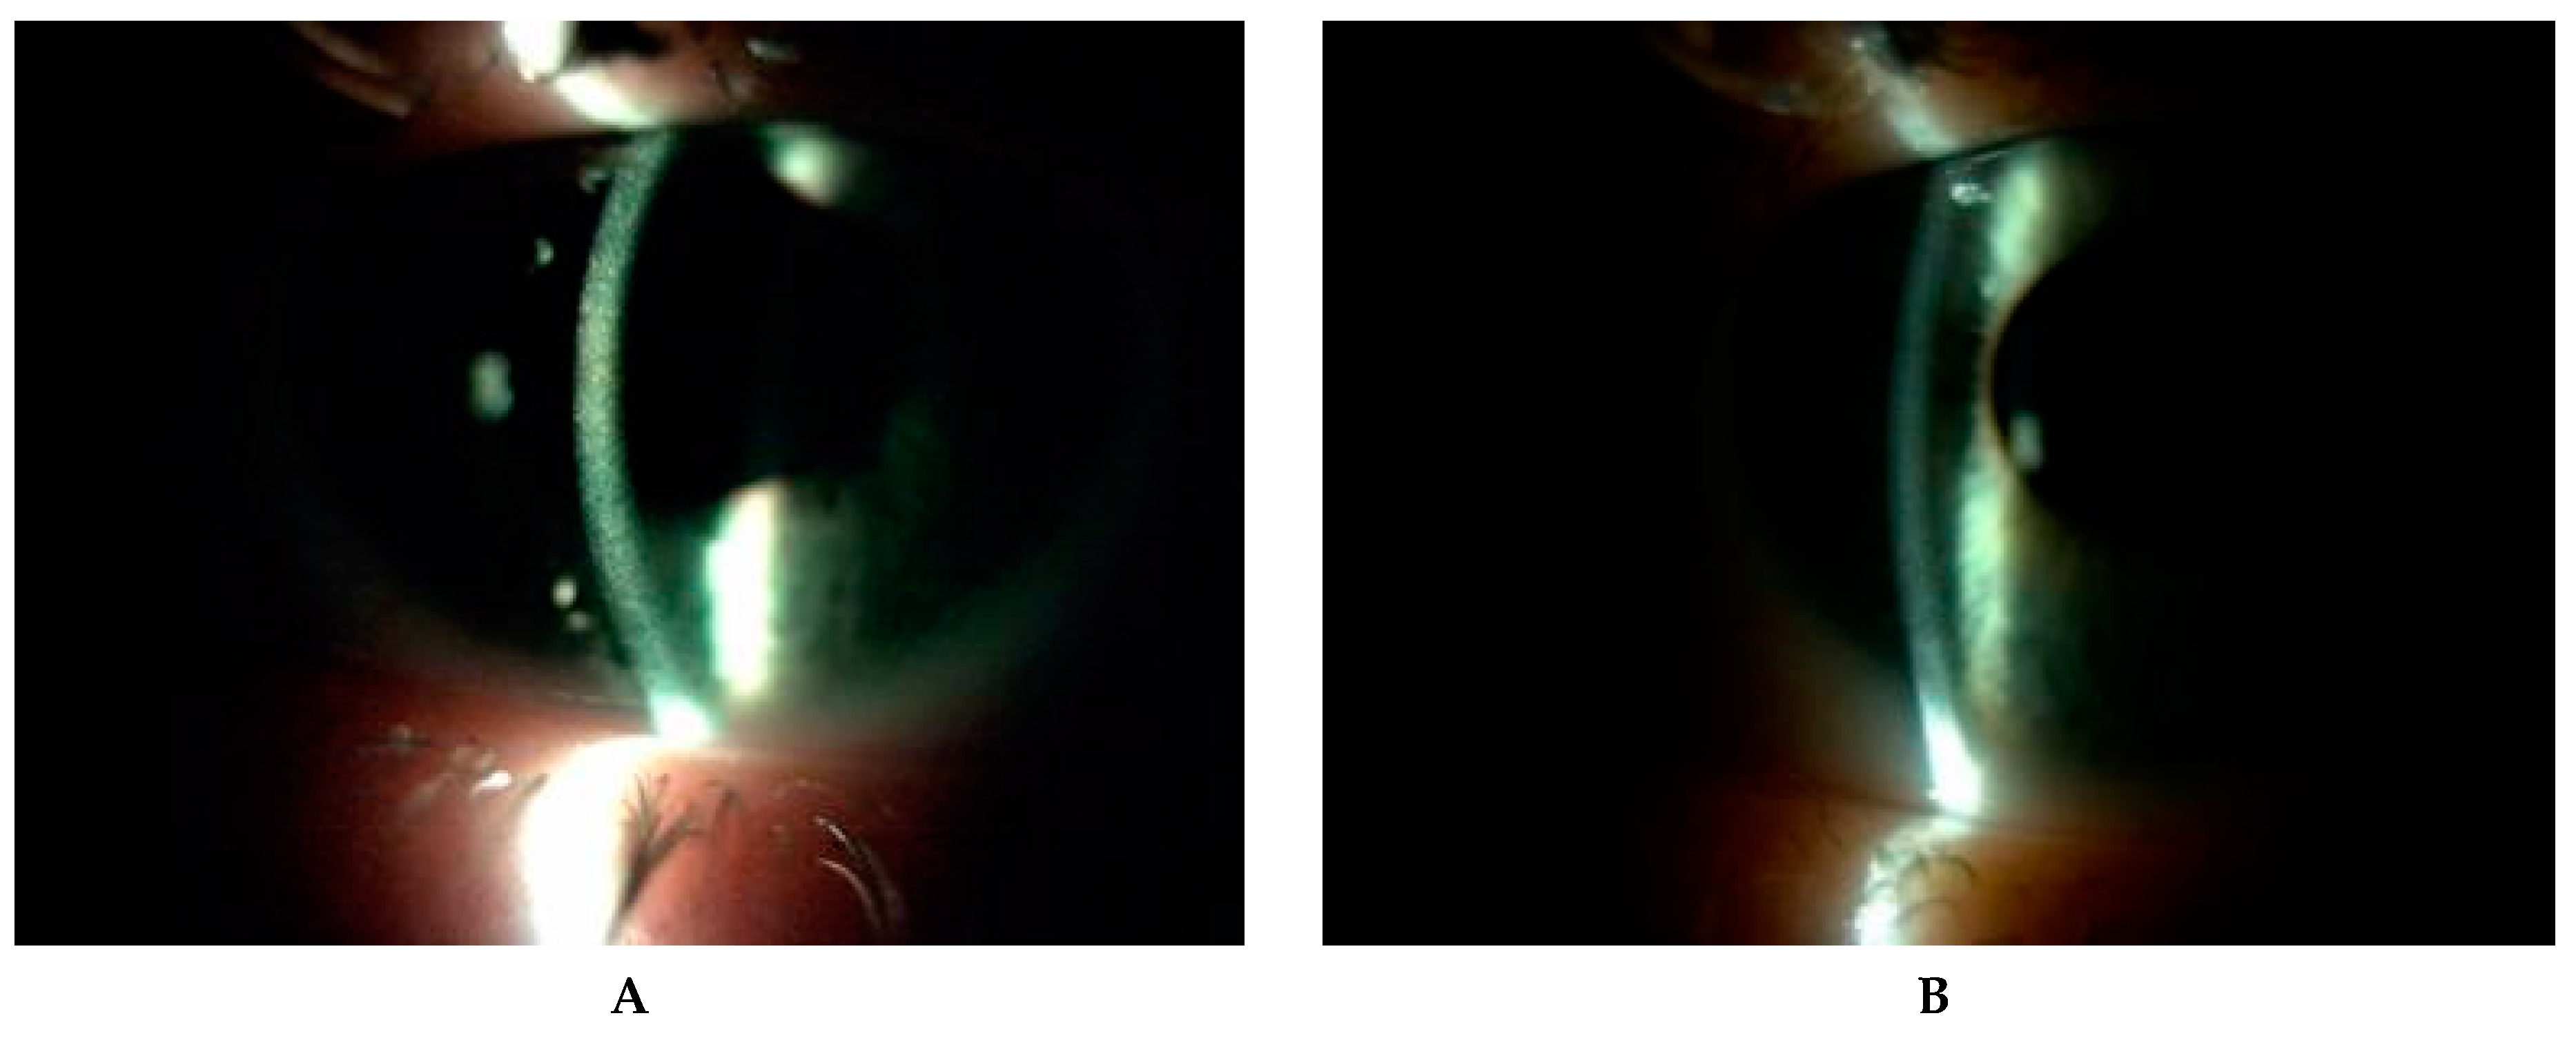

All patients underwent conjunctival examination to assess the presence of cystine crystals and level of conjunctival hyperemia (Figure 1 and Figure 2). The degree of corneal crystal deposition was assessed using Gahl’s corneal cystine crystal (CCC) score on slit lamp examination and photographs on a scale 0–3, with steps of 0.25 (based on opacity, density and number of crystals) during first visit (FV) and last visit (LV).

Figure 1. Corneal slit-lamp photographs (10–25×) of a patient (P5) with juvenile form of cystinosis. (A) View of whole cornea with crystal deposits in wide slit-lamp beam. (B) A large number of cystine deposits extending from the center to the periphery of the cornea in high magnification slit beam (25×). (C) Arrows show cystine deposits in corneal limbus and in conjunctiva (D).

Figure 6. Corneal cystine crystals in slit lamp (10×) before administration of hospital formulated 0.5% cysteamine (A) and one year after application of 0.55% Cystadrops (B) in patient 2.